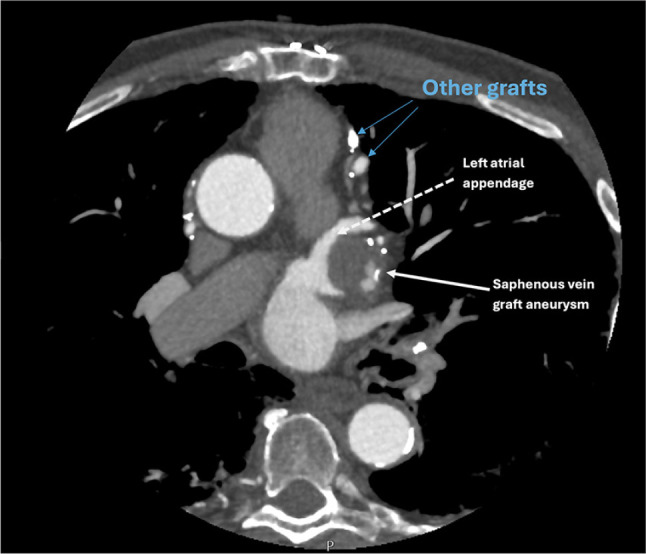

Saphenous vein graft aneurysm (SVGA) is a rare but potentially life-threatening complication of coronary artery bypass grafting (CABG). Its incidence is likely underreported due to asymptomatic cases and undiagnosed acute events. While SVGAs are more commonly associated with right atrial compression, presentation as a left atrial mass is rare. We present the case of an 85-year-old man with a history of CABG, who was incidentally found to have a left atrial appendage (LAA) density on a computed tomography (CT) chest, abdomen, and pelvis performed for unrelated symptoms of back pain and constipation. The density was initially suspected to be an LAA thrombus. However, a dedicated cardiac CT with delayed-phase imaging revealed a largely thrombosed aneurysmal saphenous vein graft to the obtuse marginal artery, which indented the LAA, mimicking an intracardiac mass. This case underscores the critical role of multimodality imaging, particularly cardiac CT, in differentiating vascular aneurysms from true intracardiac masses. Given the patient's asymptomatic status, conservative management with close follow-up was pursued. This case adds to the limited literature on SVGAs mimicking left atrial pathology and highlights the importance of recognizing this rare entity to avoid unnecessary interventions. It also emphasizes the evolving role of cardiac CT as a noninvasive, high-yield diagnostic tool for complex post-CABG anatomical assessments.

Abstract Image